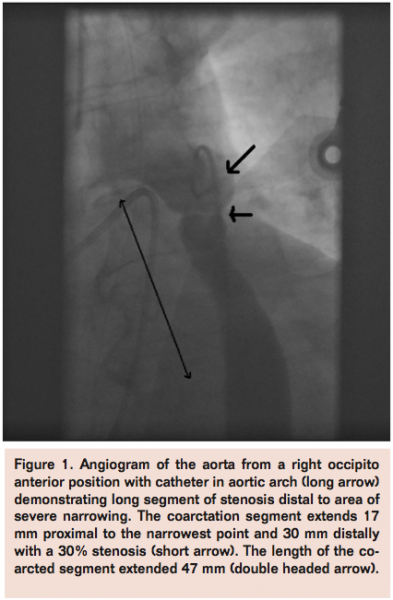

A 40-year-old male sailor was evaluated after a presyncopal episode while working on a ship. Initial examination revealed severe systemic hypertension. Follow-up evaluation by a cardiologist revealed severe coarctation. CT angiography demonstrated a well-developed left sided aortic arch with normal branching pattern (Figure 2). Though there was a discrete coarctation in the descending aorta, there was distal propagation of the stenotic area in a funnel-like fashion spanning 29 mm. The aortic isthmus proximal to the stenosis was well developed. The total length of the stenotic segment was 49 mm. The stenosis was crossed in a standard fashion and a 45 mm stent deployed with the mid-portion of the stent exactly bisecting the most stenotic area. Though the distal length of the stent did not span the entire funnel-like stenosis, it still resulted in complete relief of the stenosis. No complications were encountered and the patient’s blood pressure was significantly easier to control.